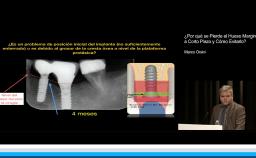

The lecturer describes a new ridge augmentation technique that is an alternative option to address atrophic ridges without the use of block grafts. The merits of osseodensification are discussed and illustrated via clinical cases with narrow ridge defects. The biology and evidence supporting this novel technique are discussed, highlighting a treatment modality that carries reduced co-morbidities to the patient, when compared to autogenous block grafts.